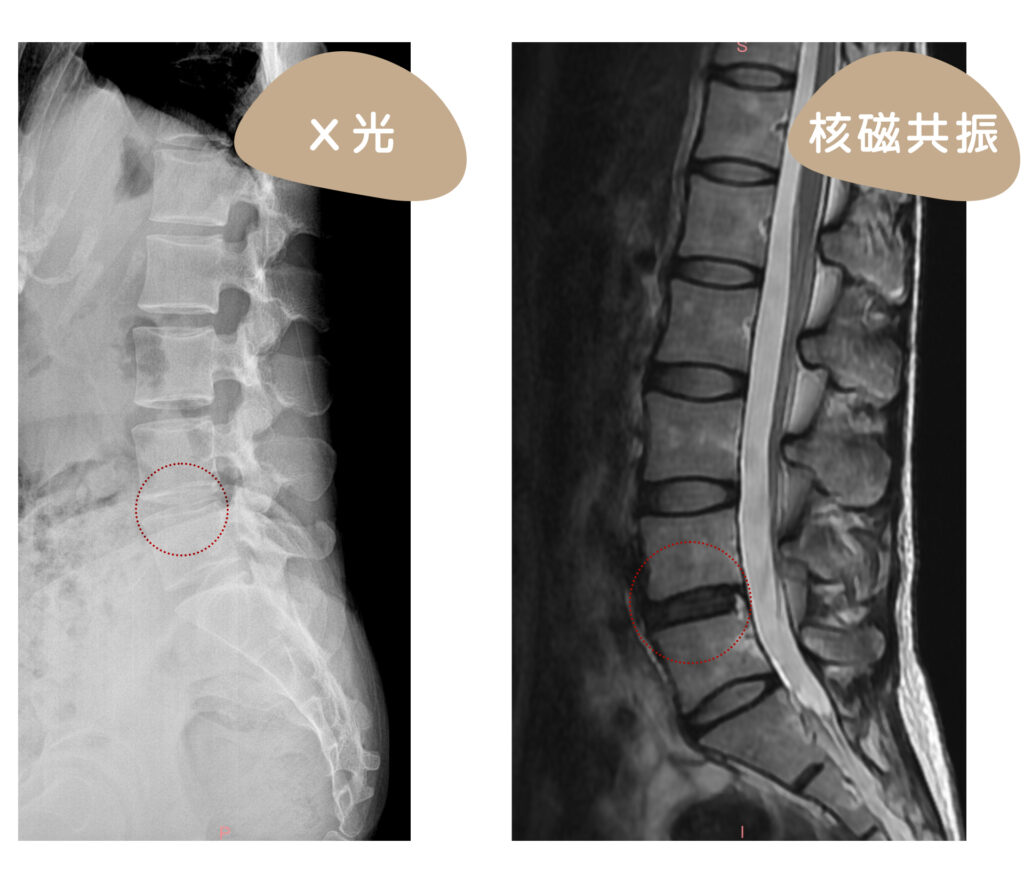

X光檢查正常怎麼辦?

X光只有等到脊椎長骨刺之後才能從增生骨以及高度減損間接得知脊椎健康度。其實脊椎常見的問題諸如:小面關節、韌帶受傷、椎間盤破裂都無法從X光上得知,還是得由醫師進行深入而詳細的檢查,並安排諸如核磁共振掃描、高解析度超音波掃描等等針對軟組織的檢查,才能找出真正病因,對症治療!